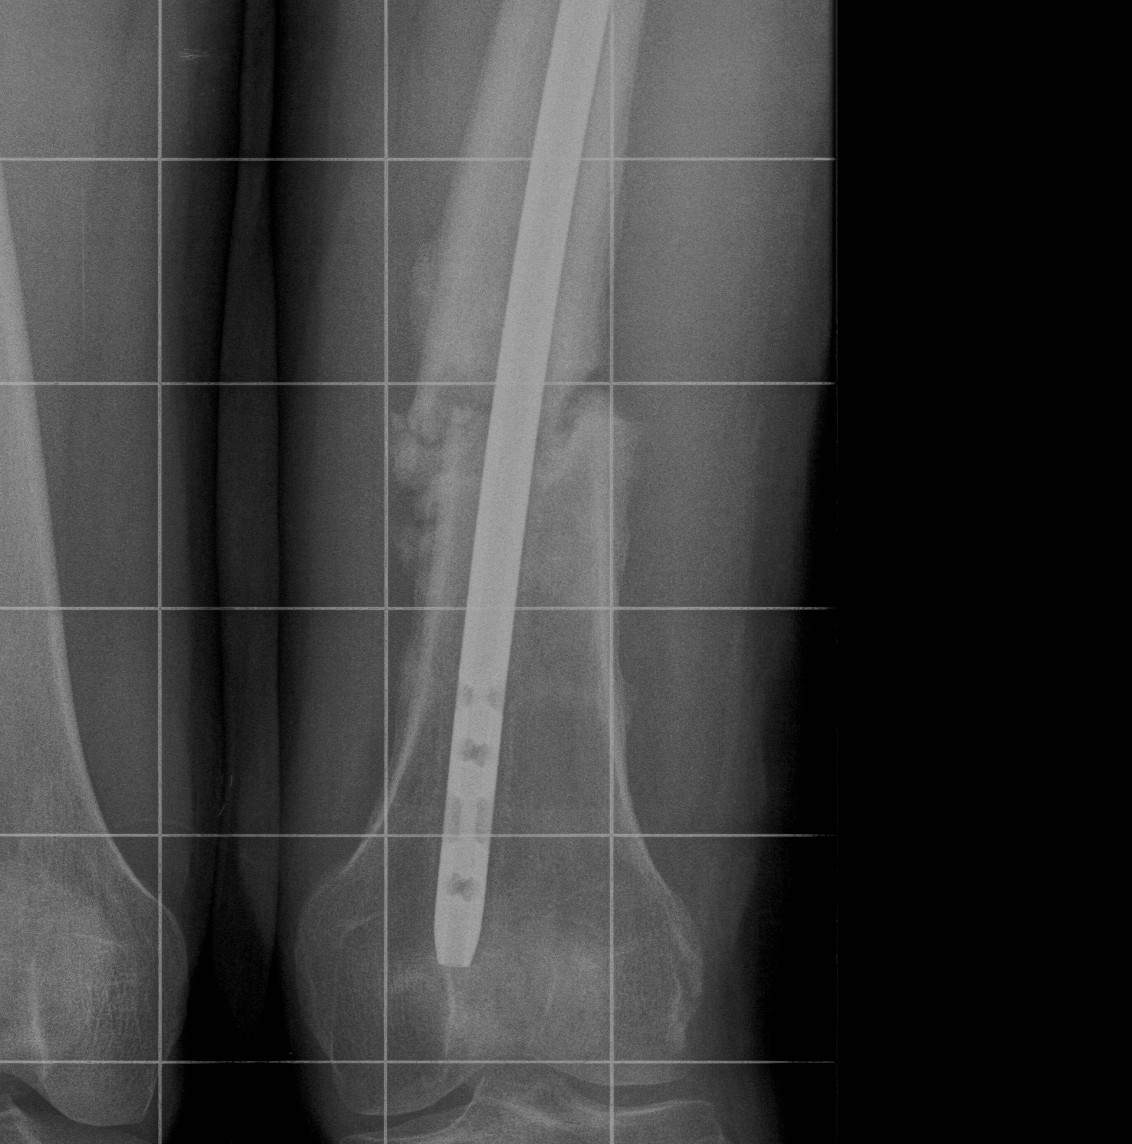

Floating Knee

Ipsilateral femur + tibial fracture

1. Floating Knee

Single incision at knee

- retrograde femoral nail

- tibial IMN if appropriate

High complication rates including non union / malunion, knee stiffness and hetertopic ossification